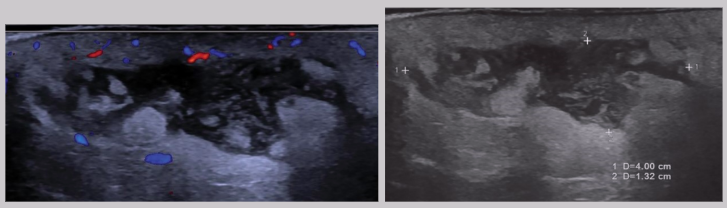

Abscess

Caused by cuts, scrapes, crushing injuries, surgical trauma, etc.

Abdominal wall abscesses are usually a surgical complication

Clinical presentation - redness, pain, swelling, elevated WBC (AKA leukocytosis)

US appearance:

Heterogeneous

Hypoechoic fluid w/ echogenic debris

Irregular borders

Posterior enhancement

Peripheral hypervascularity